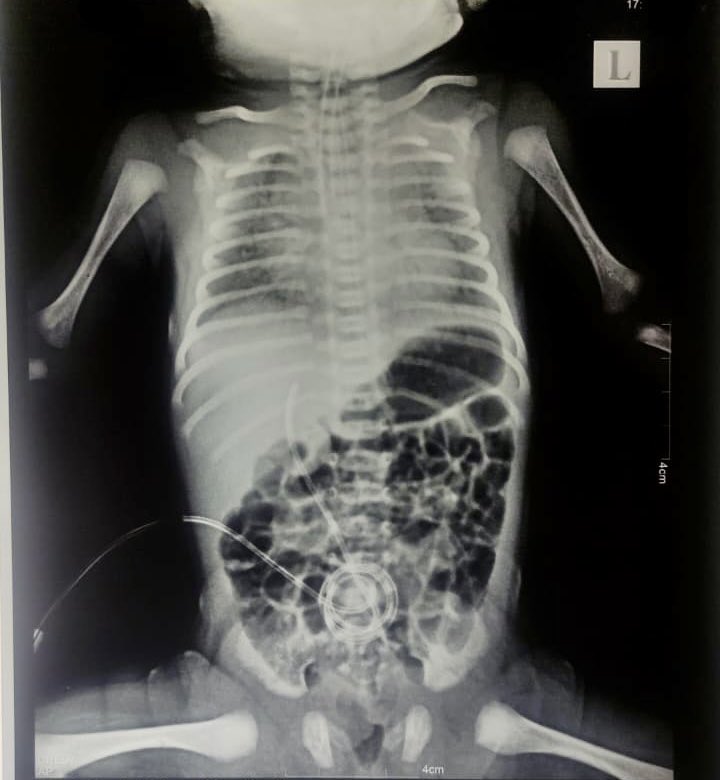

COVID-19 also impacts newborn babies. Here is an account of a 3kg full term baby delivered after a short labour and no distress to find the baby had persistent grunting and moved to the NICU ( ). 11/

The mother was fully vaccinated and had no symptoms but COVID antibodies were found in the baby and X-ray revealed totally white lungs on both sides. 12/